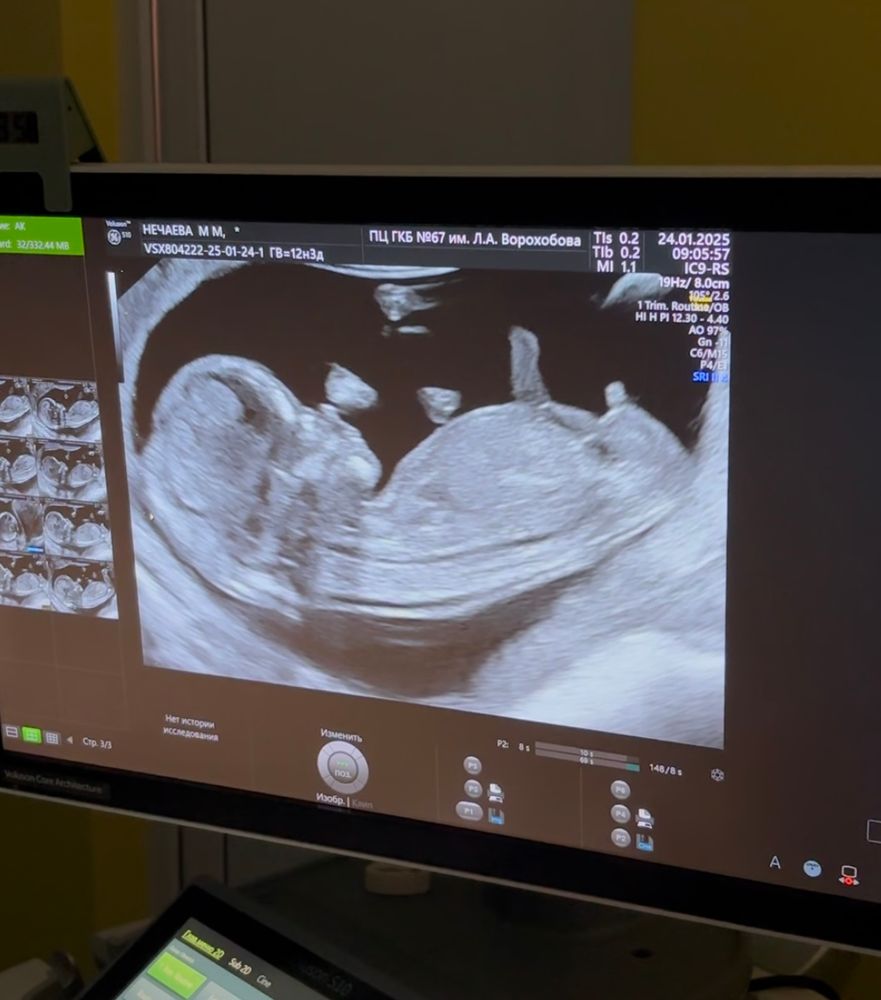

Марина в Клуб беременных 10 месяцев Точно ли мальчик?😅 Пол малыша Посмотрите еще 20 записей на эту тему Лучший ответ Незабудка Думаю мальчик 24.01.2025 Ответить Отменить Ответить Tatiana 100% 24.01.2025 Ответить коала Я б сказала что мальчик, девочкового бугорка нет 24.01.2025 Ответить Julia Tim Я думаю, что мальчик) 24.01.2025 Ответить Eva Точно мальчик 24.01.2025 Ответить Сны. Сбывались или нет? Сомнения в точности УЗИ. Чаты Беременных Выберите чат: Январята-2026 Февралята-2026 Мартята-2026 Апрелята-2026 Майчата-2026 Июнята-2026 Июлята-2026 Августята-2026